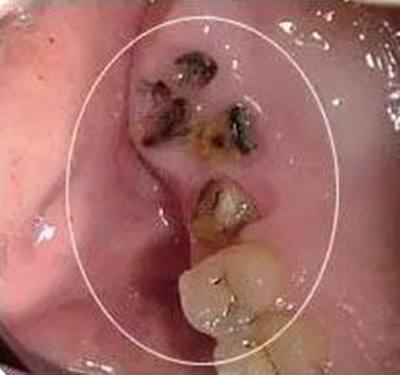

5、残根残冠。对于没有保留价值的残根残冠,建议提前拔除,以免孕期发生根尖炎;对于有保留价值,可以修复的残根残冠,要做好根管治疗,如果时间充裕,孕前做好冠修复,如果时间比较紧张,可以等生完孩子再做冠修复。